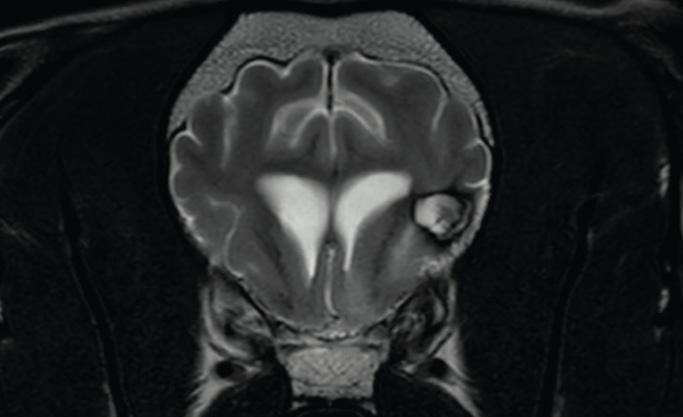

Follow-up of a patient with a glioma in the posterior part of the olfactory brain (lobus piriformis) after radiation therapy. In the picture at the top before treatment and in the picture at the bottom six months after radiation therapy; a strong reduction of the tumor size and the surrounding swelling can be seen.